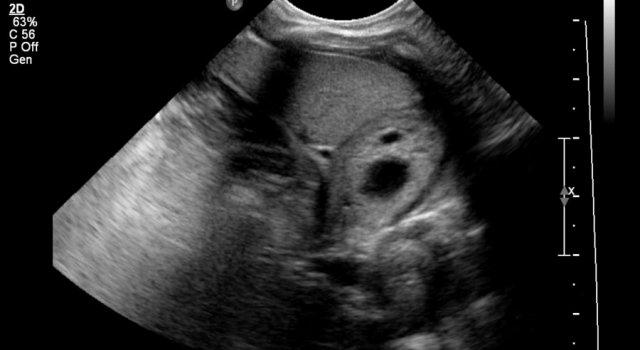

Hình ảnh của một bé trai 1 tháng tuổi được phát hiện MCKD trên siêu âm trước sinh.

Có thể thấy một ít mô thận và nhiều nang lớn.

Trên xạ hình thận với Tc-99-DMSA, không ghi nhận sự hấp thu ở phía bên trái.

Hình ảnh này phù hợp với bệnh thận đa nang loạn sản (MCKD).